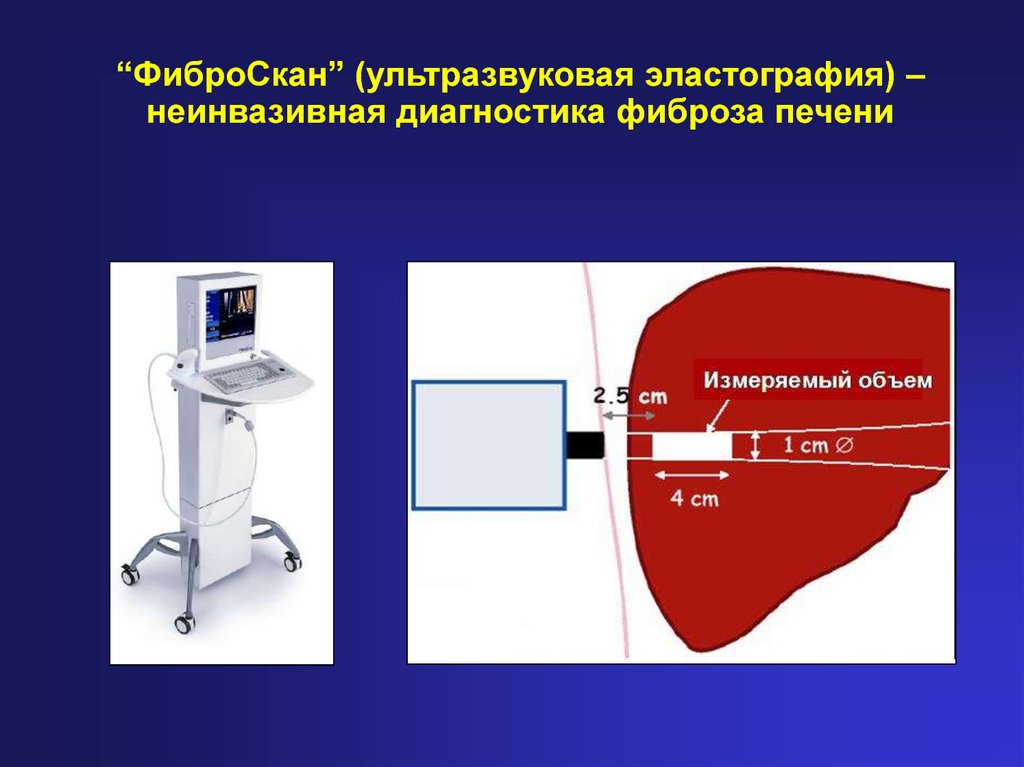

Фиброскан — это современный метод диагностики, который позволяет точно оценить степень фиброза печени с помощью транзиентной эластографии. Этот метод неинвазивен и помогает своевременно выявлять заболевания, такие как цирроз, гепатит и жировой гепатоз, без необходимости в биопсии. В этой статье вы найдете подробную информацию о процедуре, ее преимуществах и советы по подготовке к обследованию.

Эластометрия печени (фиброскан) - хороший метод для диагностики фиброза перед лечением гепатита С